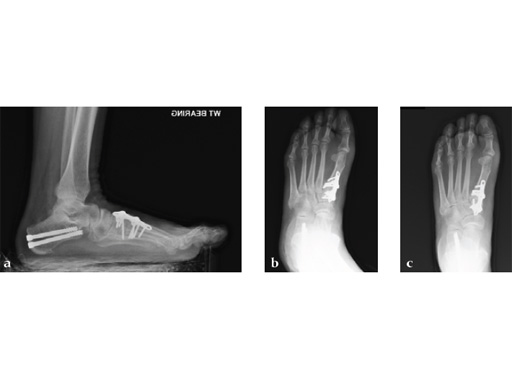

A 46-year-old obese woman with coronary artery disease had sustained a Lisfranc injury while performing an exercise program. She was unable to weight bear and used an electric scooter.

In an effort to restore her ability to exercise and taking into consideration her body weight and upper extremity weakness, a decision was made to use the variable angle locking compression plate. These postoperative x-rays were obtained at 3 months, one month after beginning weight bearing. The patients pain was reduced and she was able to resume a progressive exercise program after 4 months following surgery.

Case provided by Michael Castro, Scottsdale, Arizona